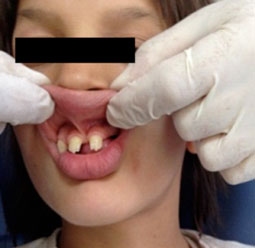

L’insertion du frein labial médian supérieur était trop basse (Fig.2) et des anomalies de forme dentaire sont observées telles que, une canine avec un aspect conique, et les bords libres des incisives supérieures festonnés (Fig.3). Sur le plan fonctionnel, la déglutition viscérale, la phonation et la mastication étaient perturbées.